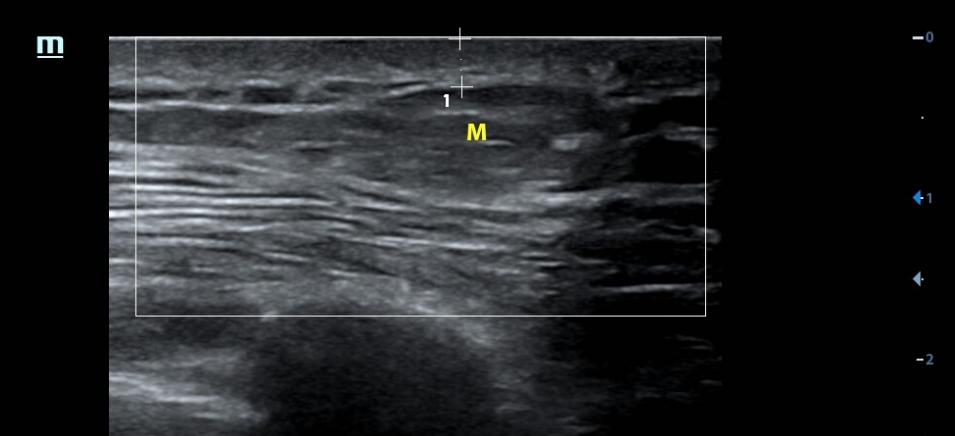

3、多条件

不同设备条件下得到的超声图像可能有很大差别,特别是肾脏血肿、肝脾挫伤。

对于外伤后患者,大量肾周血肿、明显的肝脾破裂谁都会看,但少量的肾脏血肿,隐匿性的肝肾挫伤或破裂,增益过高很可能就直接漏诊。

没有最合适的增益,只有反复调节的增益。

超声受气体、脂肪、组织密度等等等各种因素影响,同一台设备条件不一定适用所有人,每个患者都需要调节至显示清楚的条件。

对于同一个患者,不同增益下可能会给你带来不一样的信息,如果还有不会调节设备的小伙伴,可以阅读这里:0基础入门,超声设备的使用和调节